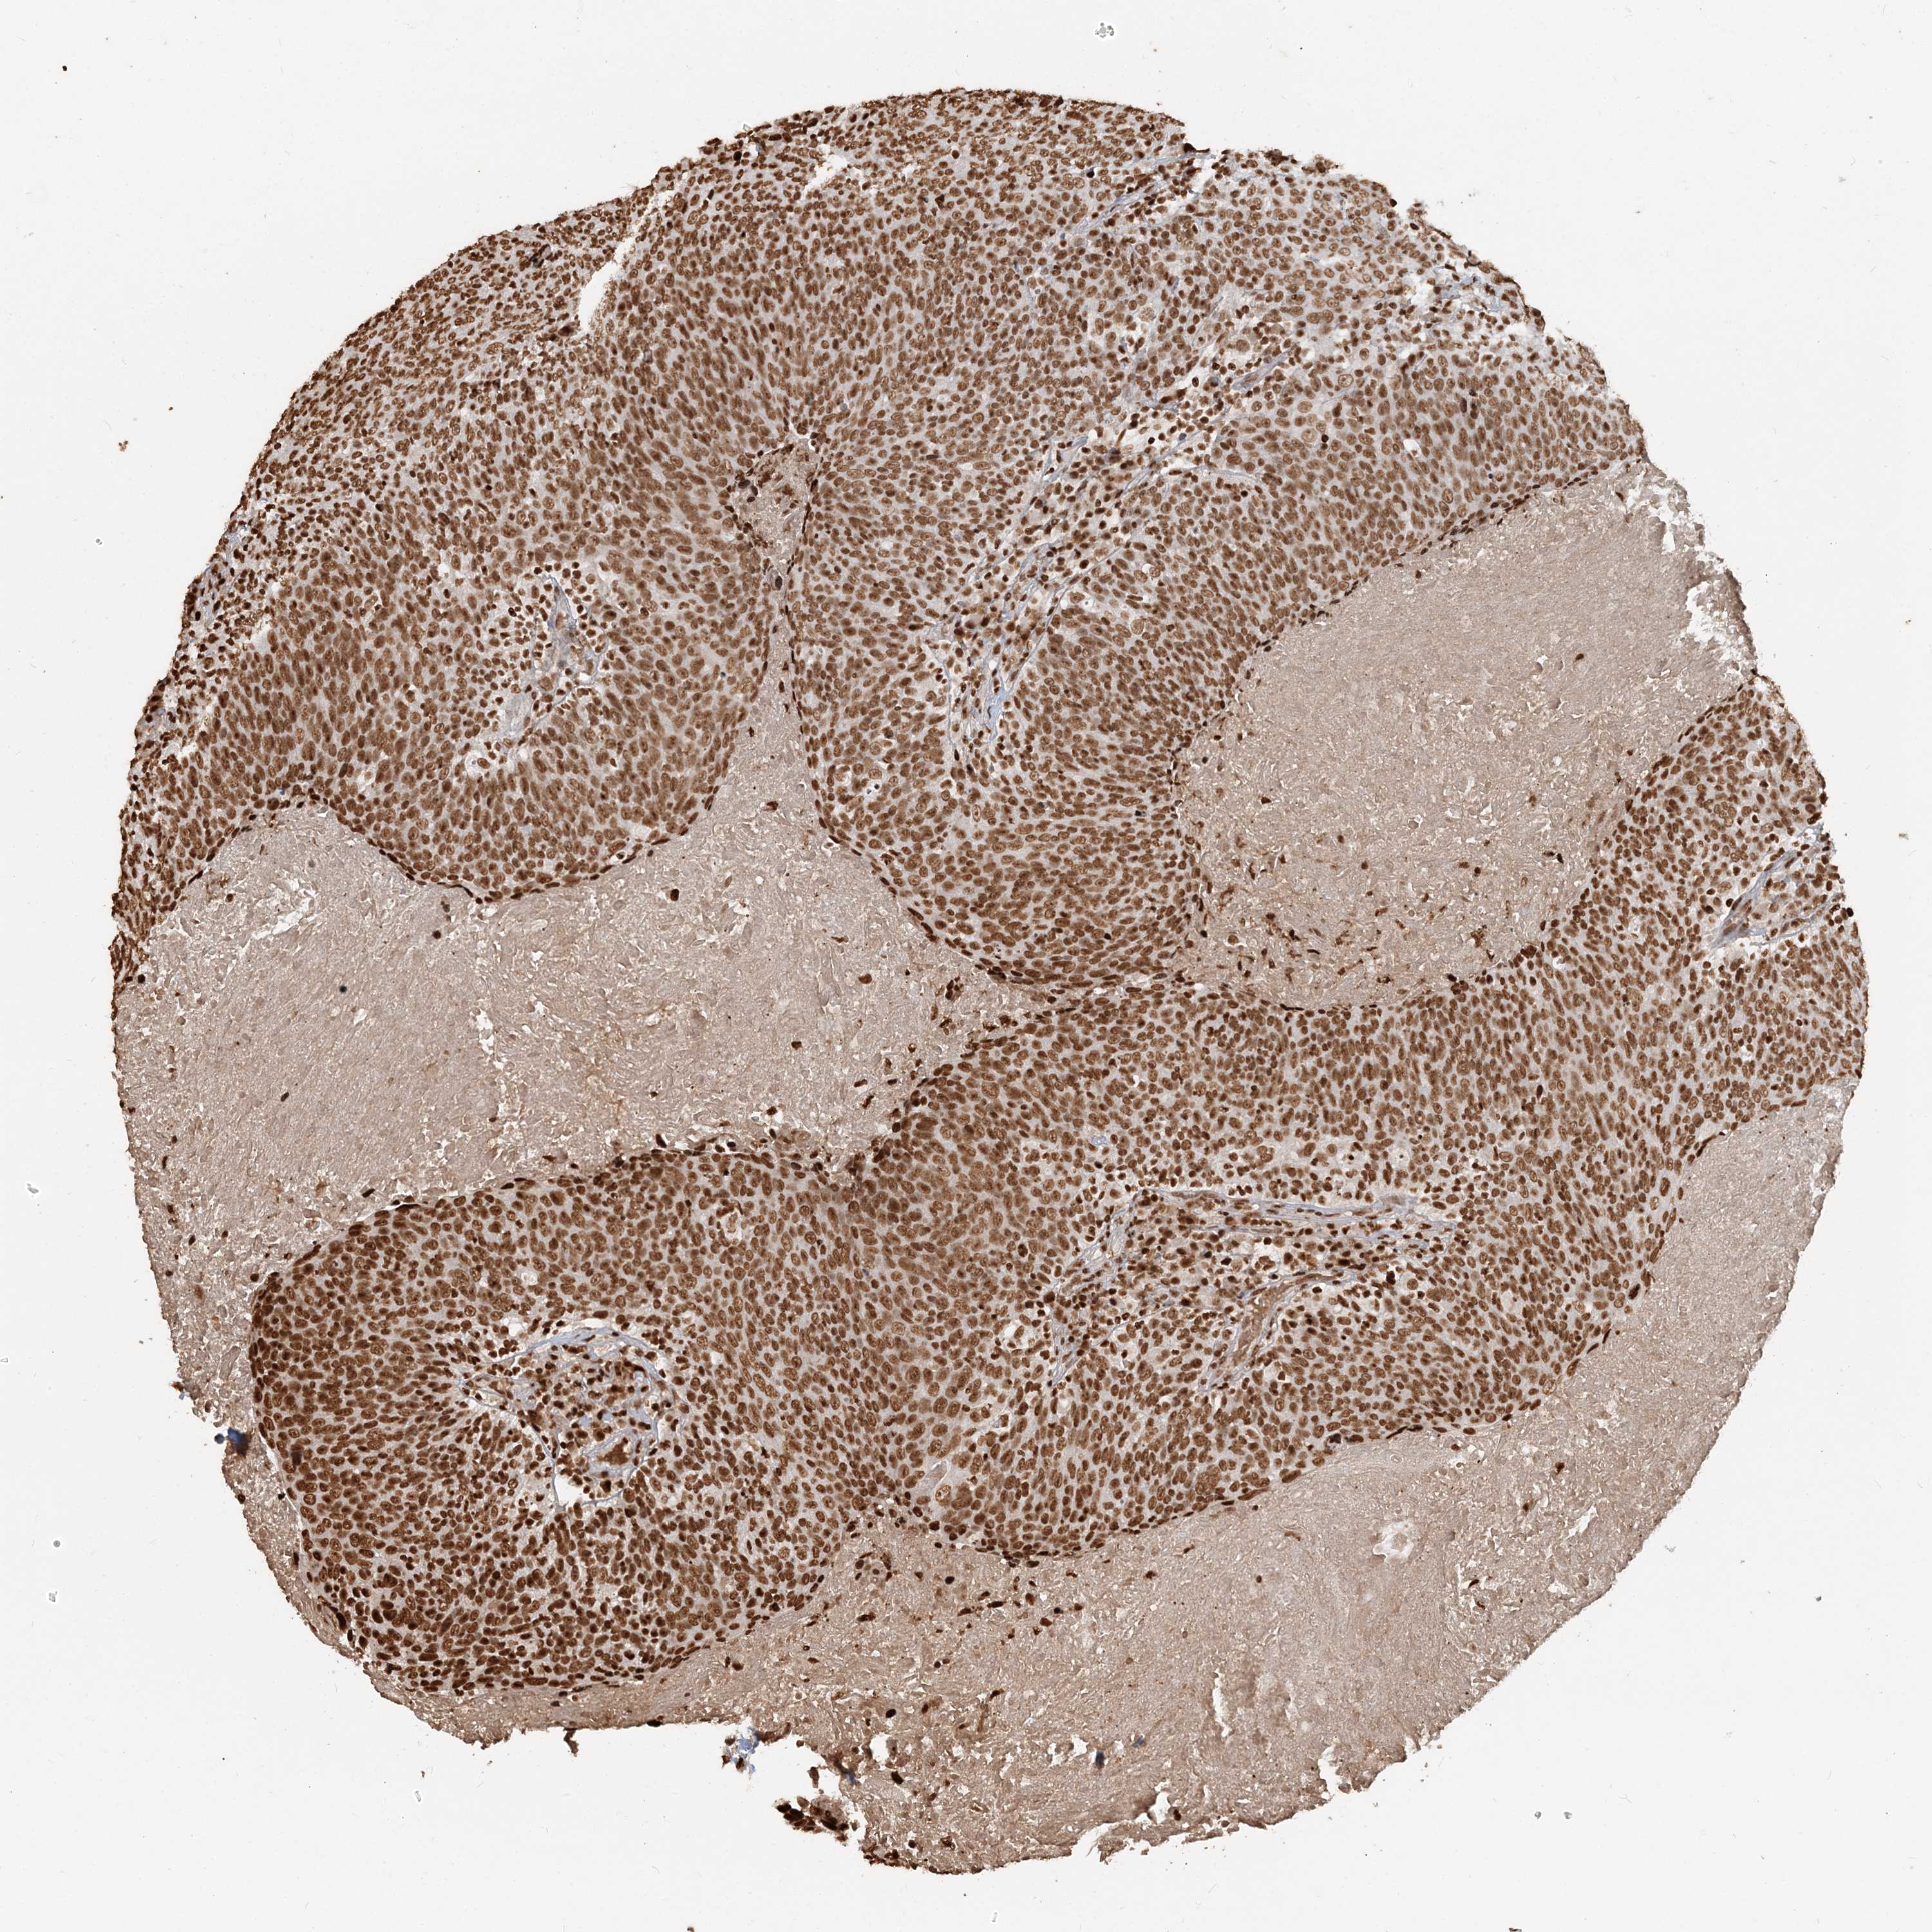

HEAD AND NECK CANCER - Protein expressioni

A mouse-over function shows sample information and annotation data. Click on an image to view it in a full screen mode. Samples can be filtered based on level of antibody staining by selecting one or several of the following categories: high, medium, low and not detected. The assay and annotation is described here.

Antibody stainingi

Antibody staining in the annotated cell types in the current human tissue is reported as not detected, low, medium, or high, based on conventional immunohistochemistry profiling in selected tissues. This score is based on the combination of the staining intensity and fraction of stained cells.

Each image is clickable and will lead to virtual microscopy that enables deeper exploration of all samples and also displays staining intensity scores, fraction scores and subcellular localization as well as patient and tissue information for each sample.

Antibody HPA042570

Antibody CAB037166

Antibody CAB037187

Antibody CAB037221

Staining

High

Medium

Low

Not detected

Intensity

Strong

Moderate

Weak

Negative

Quantity

>75%

75%-25%

<25%

None

Location

Nuclear

Cytoplasmic/membranous

Cytoplasmic/membranous,nuclear

Squamous cell carcinoma, NOS

Adenocarcinoma, NOS

Squamous cell carcinoma, metastatic, NOS

Adenoma, NOS